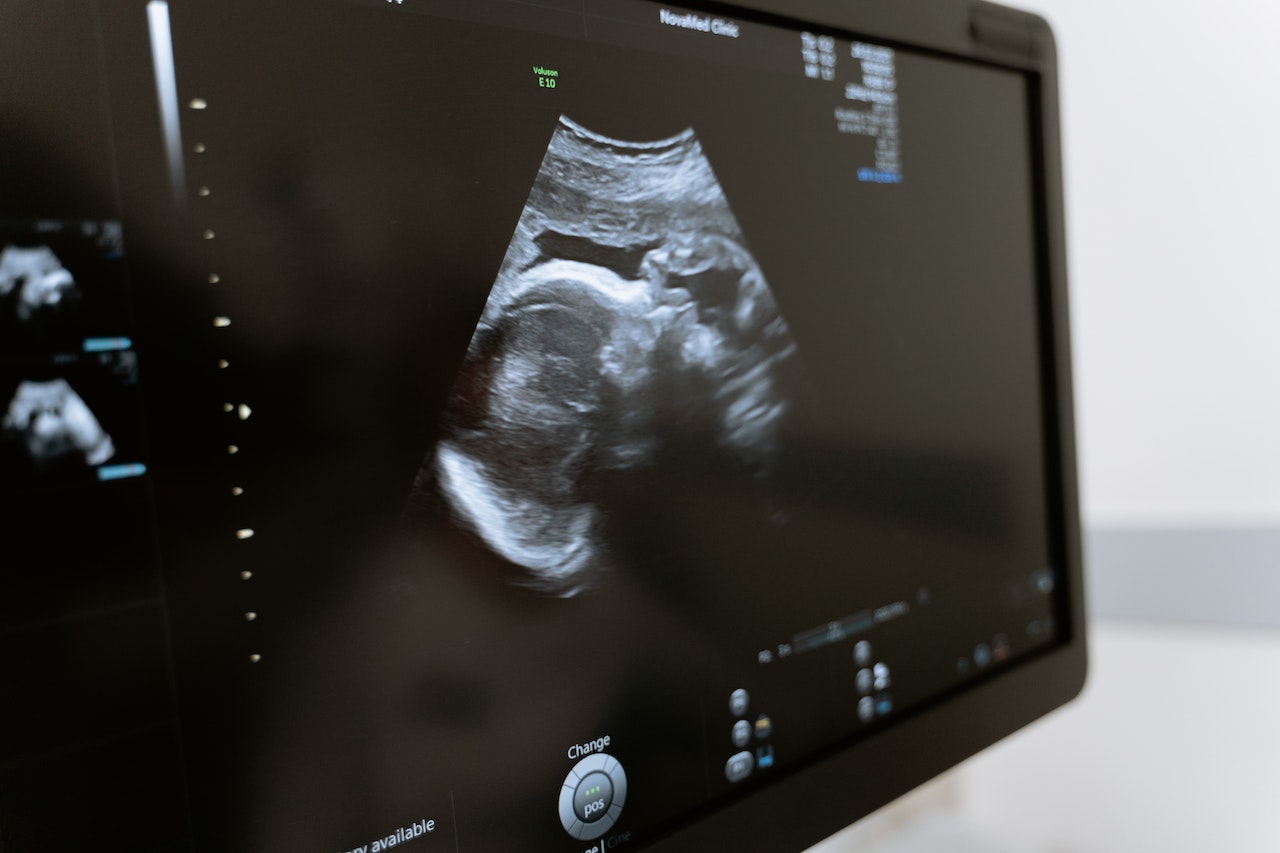

O ultrassom obstétrico é um exame de imagem que utiliza ondas sonoras de alta frequência para produzir imagens do feto dentro do útero.

Durante o exame, deve-se aplicar um gel na barriga da mãe e, em seguida, mover um transdutor sobre a pele. O transdutor emite ondas sonoras que penetram no corpo e refletem de volta pelo feto.

O transdutor capta essas ondas sonoras e as transforma em imagens que é possível visualizar em um monitor.

O ultrassom obstétrico é um exame importante para acompanhar o desenvolvimento do feto, avaliar a saúde do bebê e detectar possíveis problemas.

Ele pode ser bem útil para medir o tamanho do feto, verificar a idade gestacional, avaliar a posição da placenta e detectar anomalias congênitas.

Para fazer essas medições, o médico utiliza um aparelho de ultrassom, que emite ondas sonoras de alta frequência para criar imagens do bebê dentro do útero.

É possível visualizar todas essas imagens em um monitor, sendo que se deve fazer as medidas com ajuda de um software específico.